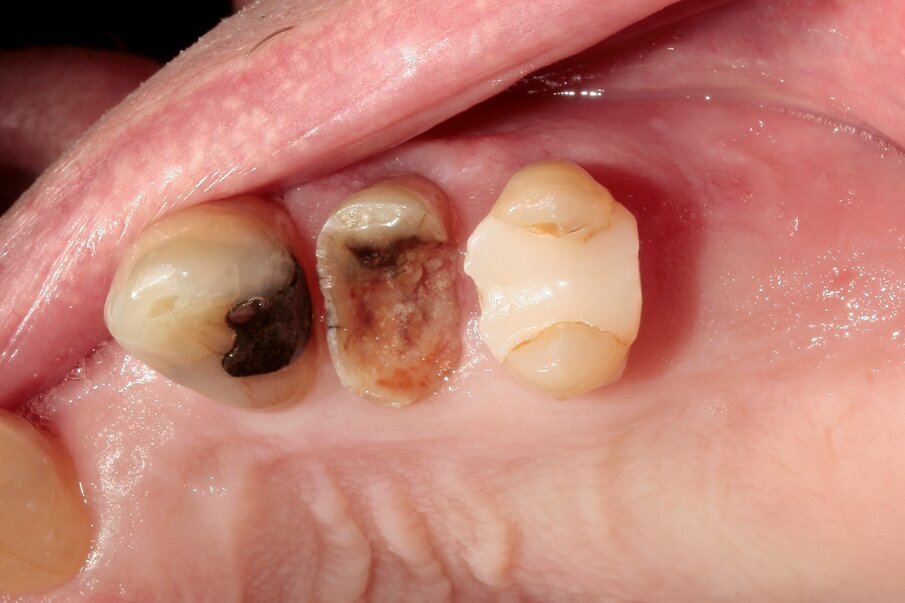

A 70-year-old female patient visited our clinic owing to a fractured maxillary first molar. Tooth #24 had previously had a large composite restoration that was no longer in place at the time of the dental appointment.

Tooth #24 was severely decayed down to the marginal bone edge.